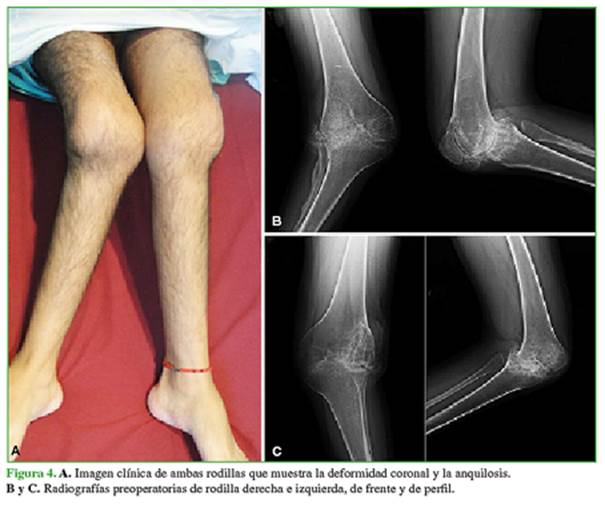

Hombre de 28 años, con antecedente de artritis reumatoide juvenil. Presenta anquilosis y valgo severo de ambas rodillas (Figura 4). En la rodilla izquierda, tiene una flexión de 70º y, en la derecha, de 60º. El KSS era 11/45 para la rodilla derecha y 15/45 para la izquierda. Refiere severas limitaciones para realizar actividades de la vida diaria.

Se realizó un RTR bilateral en un solo acto quirúrgico (Figura 5). Se utilizó una prótesis estabilizada posterior con vástagos tibial y femoral para ambas rodillas. No tuvo complicaciones en el posoperatorio inmediato ni tardío. A los cuatro años de la cirugía, el rango de movilidad es de 100° y la extensión de ambas rodillas es completa. El KSS mejoró notoriamente a 87/90 en la derecha y 80/90 en la izquierda. En las radiografías, no se observan signos de aflojamiento de la prótesis (Figura 6). Refiere estar satisfecho con el procedimiento.